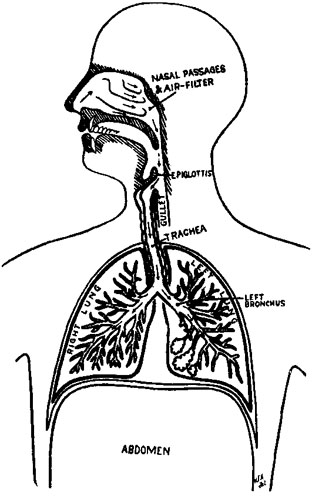

134 Diagram of the Air Tubes and Lungs

298 Bill of Health

301 Germs of Malaria